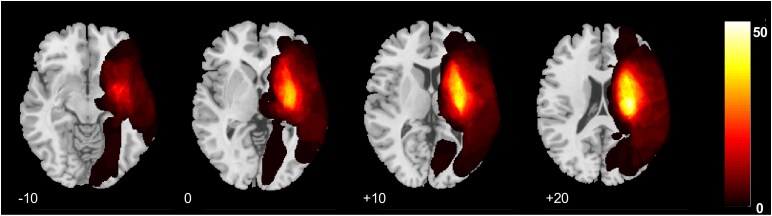

Brain age, as distinct from chronological age, may reveal post-stroke recovery mechanisms, but longitudinal studies tracking brain age are lacking. We explored longitudinal change of brain age post-stroke and its relation to upper limb sensorimotor outcome. T1-weighted MRI at baseline (∼3 weeks) and follow-up (3-7 months) post-stroke was used to estimate brain age. Difference to chronological age was calculated as brain age gap (BAG). Grey and white matter changes and lesion location related to increased brain ageing were investigated, controlling for lesion volume. Association between BAG change and upper limb sensorimotor outcome was studied using linear mixed effects regression. Totally, 114 stroke patients with arm/hand hemiparesis were pooled from three studies. BAG significantly increased from baseline to follow-up, a period of ∼6 months, by a mean of 3.62 years (t = -7.31; P < 0.001). Voxel-based morphometry showed that high BAG change was related to reduced grey and white matter volume ipsilesionally, extending beyond the stroke lesion. Voxel-based lesion symptom mapping showed that lesion to thalamocortical projections, internal capsule and corona radiata related to accelerated brain ageing. BAG change was significantly associated with motor outcomes in the sub-acute to chronic phase, as expressed by Fugl-Meyer assessment (β = -5.62, SE = 2.81, t = -2.00, P = 0.05), maximum grip strength (β = -0.14, SE = 0.04, t = -3.36, P = 0.001) and dexterity assessment (β = -0.09, SE = 0.04, t = -2.17, P = 0.03). We demonstrate increased brain ageing within the first few months post-stroke. This secondary neurodegeneration was negatively related to motor outcome. Brain age may be a valid whole-brain probe of individual secondary post-stroke degeneration, relevant for predicting recovery and identifying targets of neural plasticity.